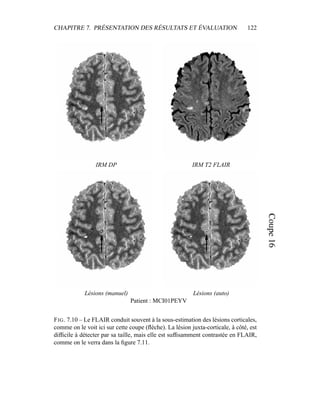

– puisque notre but est d’obtenir un critère sur l’intensité qui sera raffiné ensuite

par contraintes spatiales.

Dans sa formulation la plus simple, le processus de segmentation prend un

ensemble multi-séquences à segmenter – les deux images T2 / densité de pro-